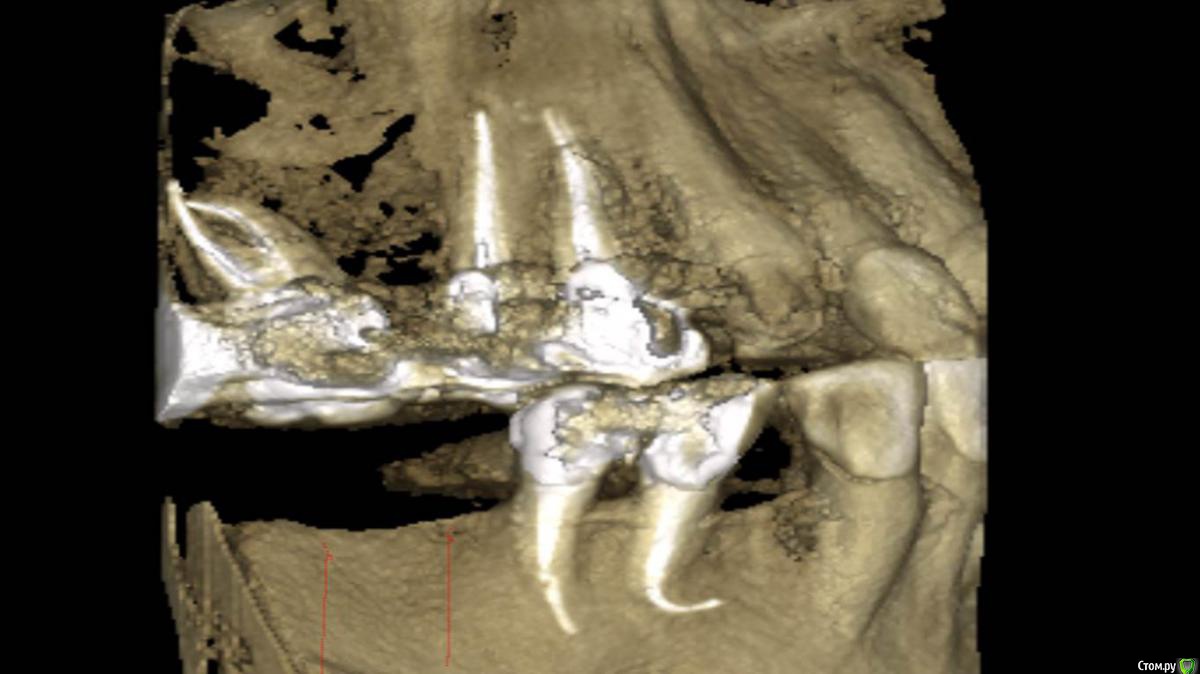

Сегодня пришёл мой давнишний  пациент... по поводу возможной имплантации....

и вот какой ...крючок на КТ ,,я обнаружил (вспомнил) ..Эндолечение 4.5  проводилось 6-7 лет назад :)

Пока полет нормальный